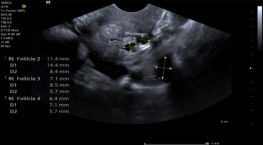

syngo® Auto Follicle 自动卵泡评估

‒ 快速、精确的评估多个卵泡

‒ 自动获取和记录测量数据

‒ 节省检查时间